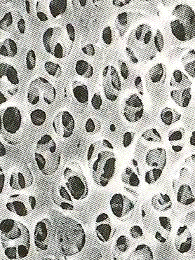

Приложение № 2: Виды мембранных фильтрующих перегородок

А                                                     Б

А - двухслойная мембрана из полиамида - размер пор 0,45/0,2 мкм.

Б - двойная гетерогенная мембрана из ацетата целлюлозы - размер пор 0,65/0,2 мкм.